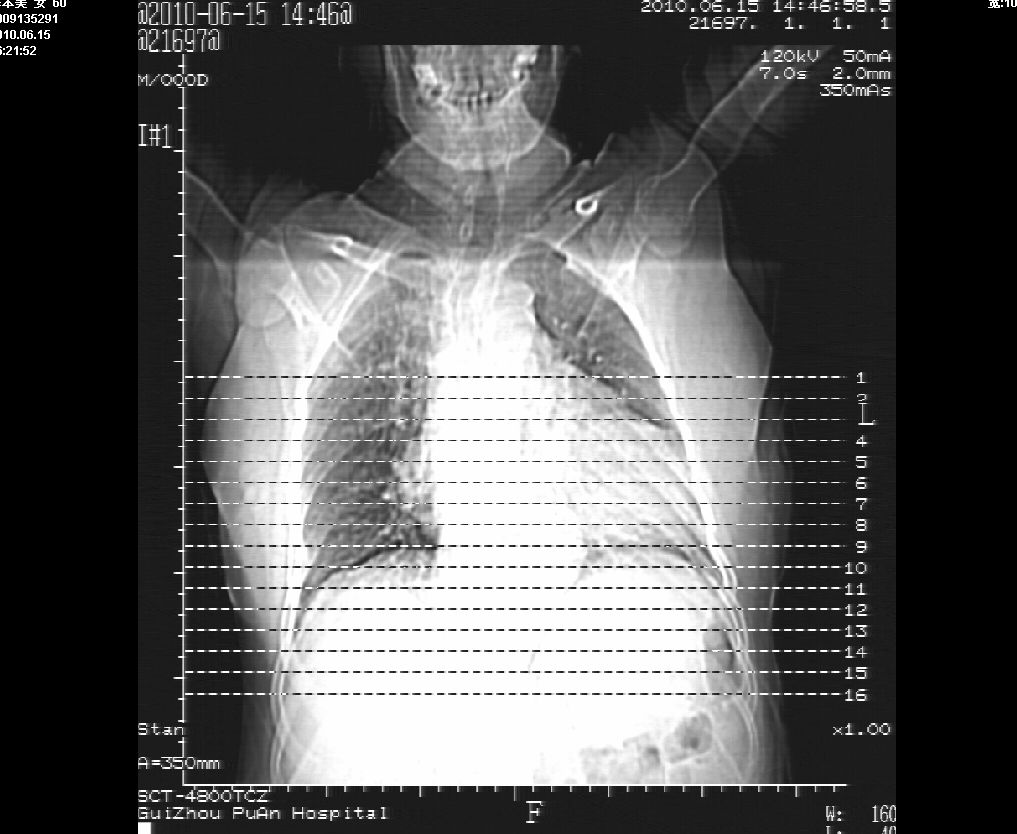

李某,60岁,女,胸闷气促一月,照片发现心后缘圆形高密度影,ct扫描如下。请大家看看,描述一下,给个诊断意见。

降主动脉夹层动脉瘤,建议增扫

占位或夹层动脉瘤,增强扫描

图像欠清,主动脉瘤?食管肿瘤?食管裂孔疝?建议增强。

支持夹层动脉瘤,建议cta。

主动脉瘤?食管肿瘤?食管裂孔疝?建议增强。